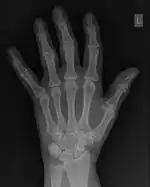

![]() Fig. 1.28(a): A radiograph of the wrist. | ![]() Fig. 1.28(b): The wrist radiograph processed by attenuating periodic structures of size between 1 and 10 pixels. |